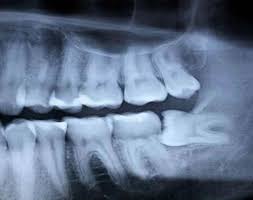

But seriously–just in case you didn’t know, I had my wisdom teeth removed a couple days ago. It was worse than a normal removal because my bottom teeth were sideways and the roots were hooked into my inferior alveolar nerve.

The dentist told me I would likely have permanent nerve damage after the procedure. He said it wouldn’t effect my speech or my smile, but I would lose feeling to my lower jaw and lips. He said most people can recover (after 6 months to a year) and regain feeling, but that there was a real possibility I wouldn’t ever have proper sensation ever again.

Plus, if I didn’t get them removed, the teeth would impact all the other ones and destroy the roots to my lower teeth. Fantastic.